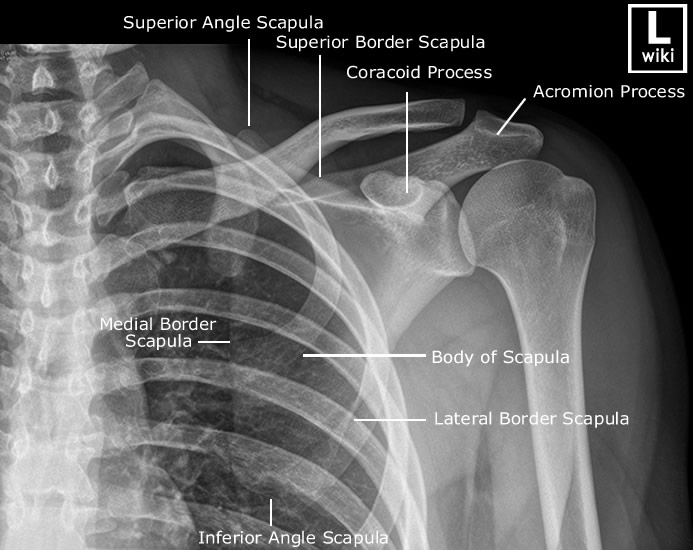

Scapula Hardest Bone To Break. Scapula fractures are uncommon fractures to the shoulder girdle caused by high energy trauma and associated with pulmonary. A scapula fracture is a break or crack in the scapula (shoulder blade), which is a flat, triangular bone providing attachment to the muscles of. Pain, swelling and bruising are the most common symptoms. The shoulder is made up of three bones: Direct trauma is usually the cause of most scapula fractures. Nonoperative treatments include the use of a sling or shoulder immobilizer, ice and pain medications. Shoulder trauma (fractures and dislocations) trauma to the shoulder is common. Only about 10 percent of scapula fractures require surgery. A scapula fracture usually occurs due to a direct blow to the shoulder blade, such as a motor vehicle accident, a hard ball impact in. Scapula fractures are often accompanied by fractures to the ribs and/or other bones in the shoulder due to the high energy required to.